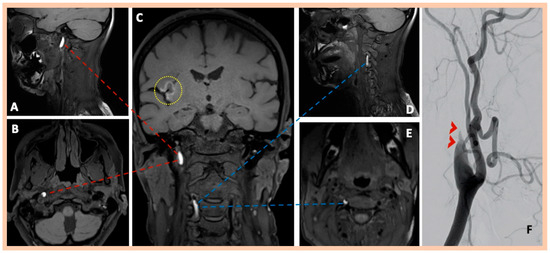

| Pat. #6 | 42 | M | Unremarkable | No | Left frontal headache, vision disturbances, left-sided sensory deficits | Yes (confirmed in DSA) | Dual antiplatelet therapy (Clopidogrel 75 mg/day plus Acetylsalicylic acid 100 mg/day) for 21 days, followed by Clopidogrel 75 mg/day | Substantial clinical recovery—NIHSS: 0 at discharge | 0 |

| Pat. #6 | Chronic ischemic lesion in the right inferior frontal gyrus | Focal stenoses along the distal cervical segments of the right and left ICA | Intimal flap along the distal cervical segment of the right ICA Intramural hematoma along the distal cervical segment of the left ICA | DSA confirmed the findings | Right and left ICA dissections | 2 | Yes—wall abnormalities along the right renal artery, indicative of fibromuscular dysplasia |

| Pat. #7 | Yes—multiple ischemic lesions in different arterial territories | Stenoses along the cervical segments of the right and left ICA. Characteristic “string-of-beads” appearance along the cervical segment of the left ICA | Intramural hematoma along the cervical segment of the right ICA. Intramural hematoma along the cervical segment of the left ICA, combined with the typical beaded appearance | DSA confirmed the findings and also revealed a focal stenosis of the right renal artery | Asymptomatic right and symptomatic left ICA dissections | 2 | Yes—focal stenosis of right renal artery |